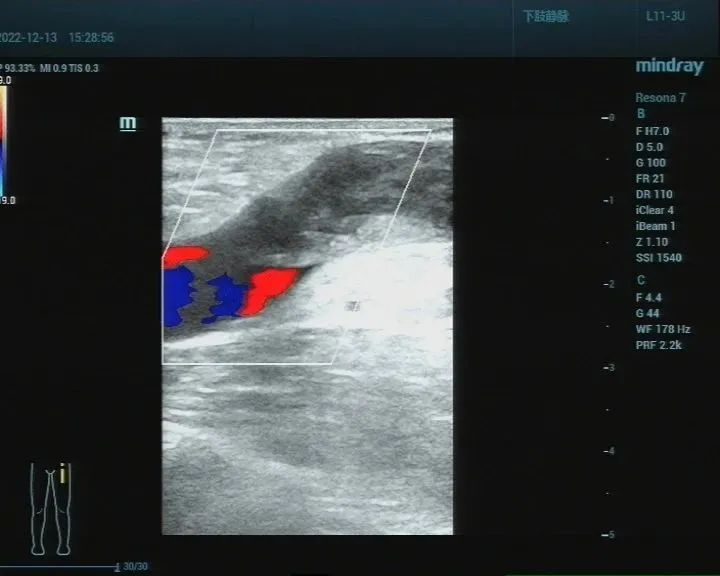

超声医生利用彩超仪器获得血管的实时动态图像,观察血管的解剖结构、血流动力学状态来诊断疾病。由于它方便快捷、无创、没有辐射等优点,血管超声检查又被称为无创伤性的血管造影术。临床医生常把它作为对头颈部及四肢血管疾病的首选检查。

(3)四肢静脉疾病:如有手脚肿胀、疼痛、“蚯蚓样”包块等症状,疑为静脉血栓、静脉瓣功能不全引起。